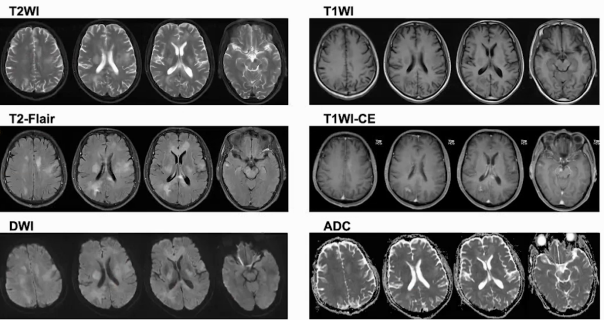

颅脑磁共振可见双侧额顶叶区域椎体束、胼胝体、右侧丘脑及脑干多发斑片状稍高信号,胼胝体压部异常信号影,Flair呈高信号,弥散轻度受限。增强扫描部分强化,灌注成像CBV、CBF稍增高,SWI未见明显出血及顺磁性沉着,MRS见Cho峰升高,NAA峰降低,局部Cho/NAA比值大于2,可见典型脂峰。

病灶累及范围深且相对对称,以双侧顶叶、额叶椎体束、前肢体、右侧丘脑、脑干等区域为主,部位和年龄与淋巴瘤相符,累及胼胝体膝部可见蝶翼征,增强扫描也符合淋巴瘤特征,但未见到典型的明显灌注减低,属不典型特征。